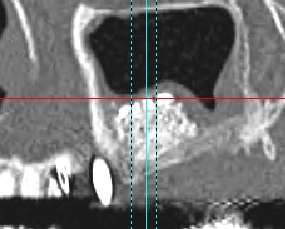

Photos extraites de la vidéo :

7 mois pot-op